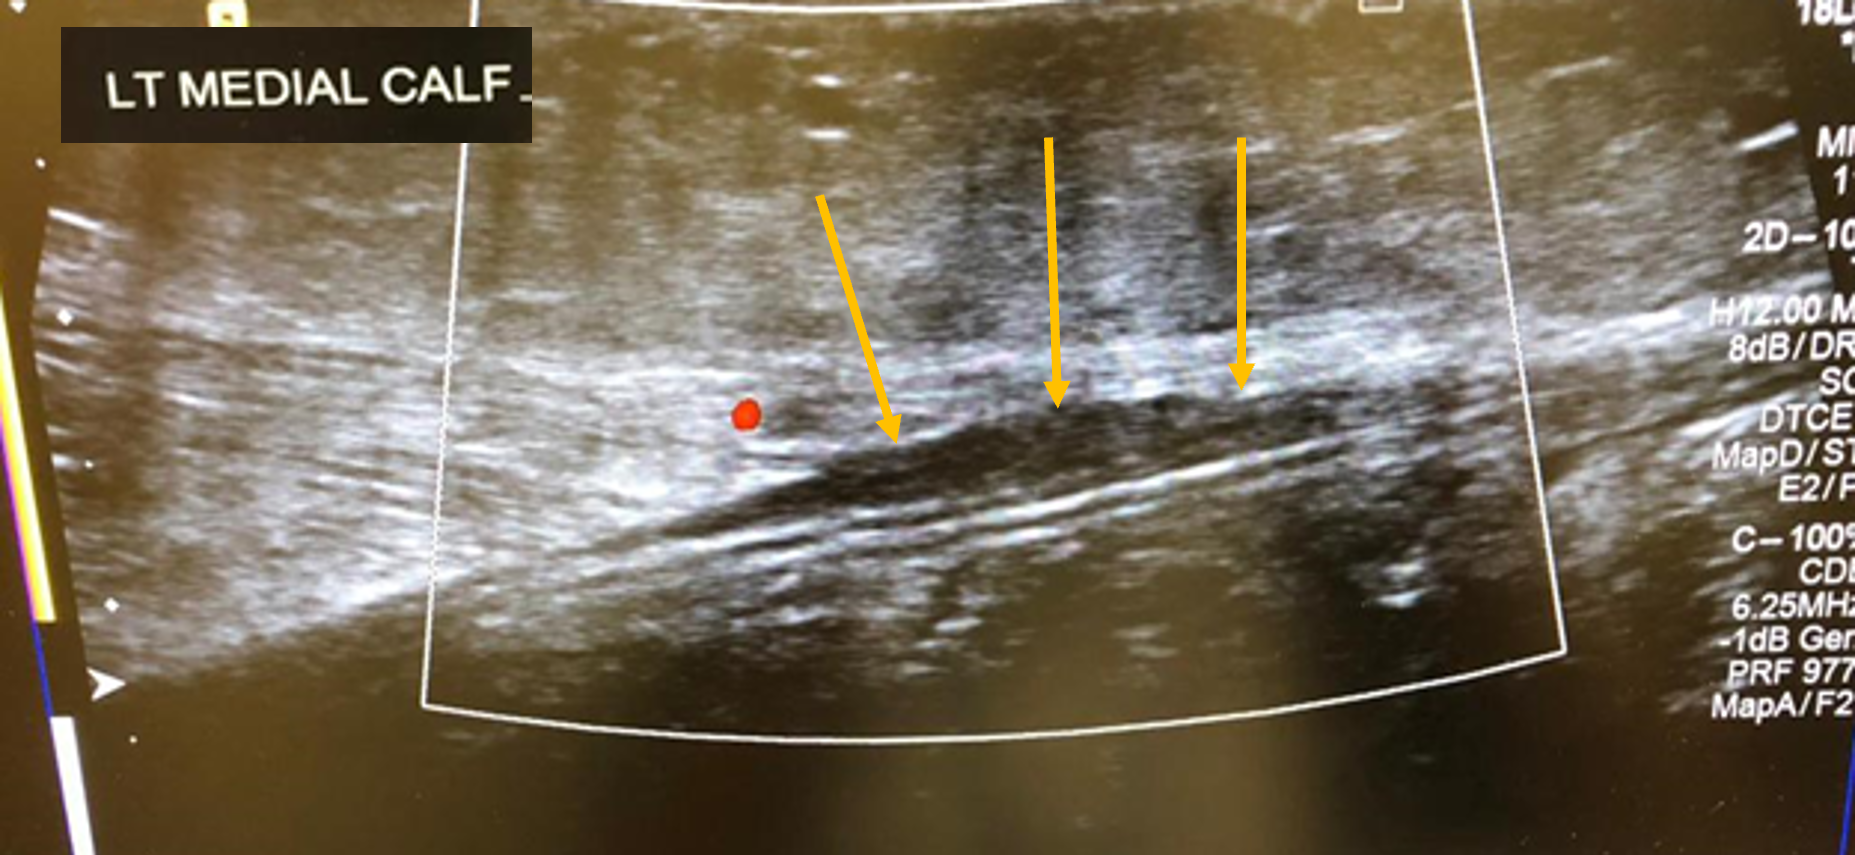

Although classically seen in people who play tennis, it can also be induced by playing squash, skiing, and athletics. Therefore, it typically occurs in active individuals. Extension of the knee and forced dorsiflexion of the ankle seem to be the most frequent biomechanical causes of the injury, which result in rupture of the medial head of the gastrocnemius muscle or injury to the gastrocnemius-soleus aponeurosis, without evidence of muscle rupture.

Ultrasound findings show a hypoechoic linear abnormality (yellow arrows).